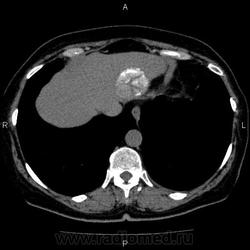

- https://radiomed.ru/sites/default/files/styles/case_slider_image/public/user/5278/10004_1.jpg?itok=lJwqd0kF

Это кальцификация. Бывшая гематома, бывший воспалительный процесс, паразитарное поражение, гемангиома, сосудистая мальформация, злокачественное нечто либо метастаз. Без клиники, пола, возраста и болюсного КТ... ну допустим, я поставлю на солитарный метастаз. И это 50/50, т.е. либо я права, либо нет.

гидативную нежизнеспособную кисту. Гемангиома гиподенсна относительно здоровой паренхимы, да и гематома так выглядеть не может.

На эхинококковую кисту похожа

Похоже на кальцинированную эхинококковую кисту печени; для уточнения КТ с болюсным мультифазным контрастированием; консультации гастроэнтеролога и онколога.

"Образование" 3 года без динамики. На УЗИ написали гемангиому. Спасибо всем.